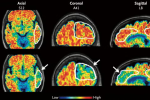

أحد العلماء يتفحص أنماطاً تظهر في الدماغ لدى مريض ألزهايمر (رويترز)